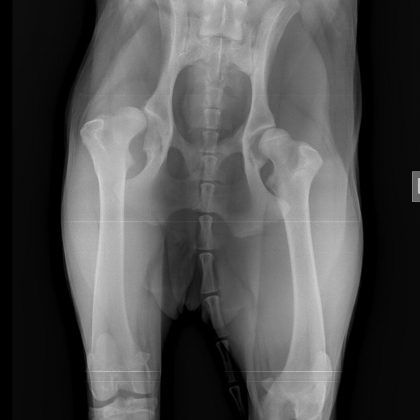

Prilažemo vam fotografije. Na prvoj je mail od veterinara iz Slovenije koji preporuča operaciju, na drugom je račun iz veterinarske ambulante u Zagrebu kada je dijagnosticirana bolest i treći je rengenska snimka problematičnog kuka kujice.